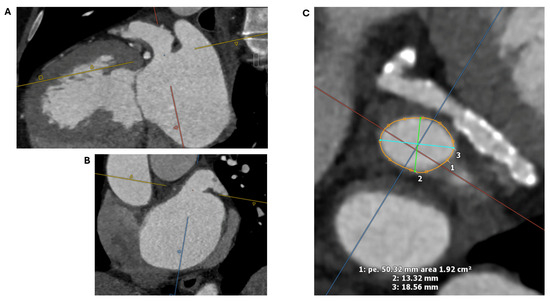

2.1. Cardiac CT

2.1.2. LAA Measurements